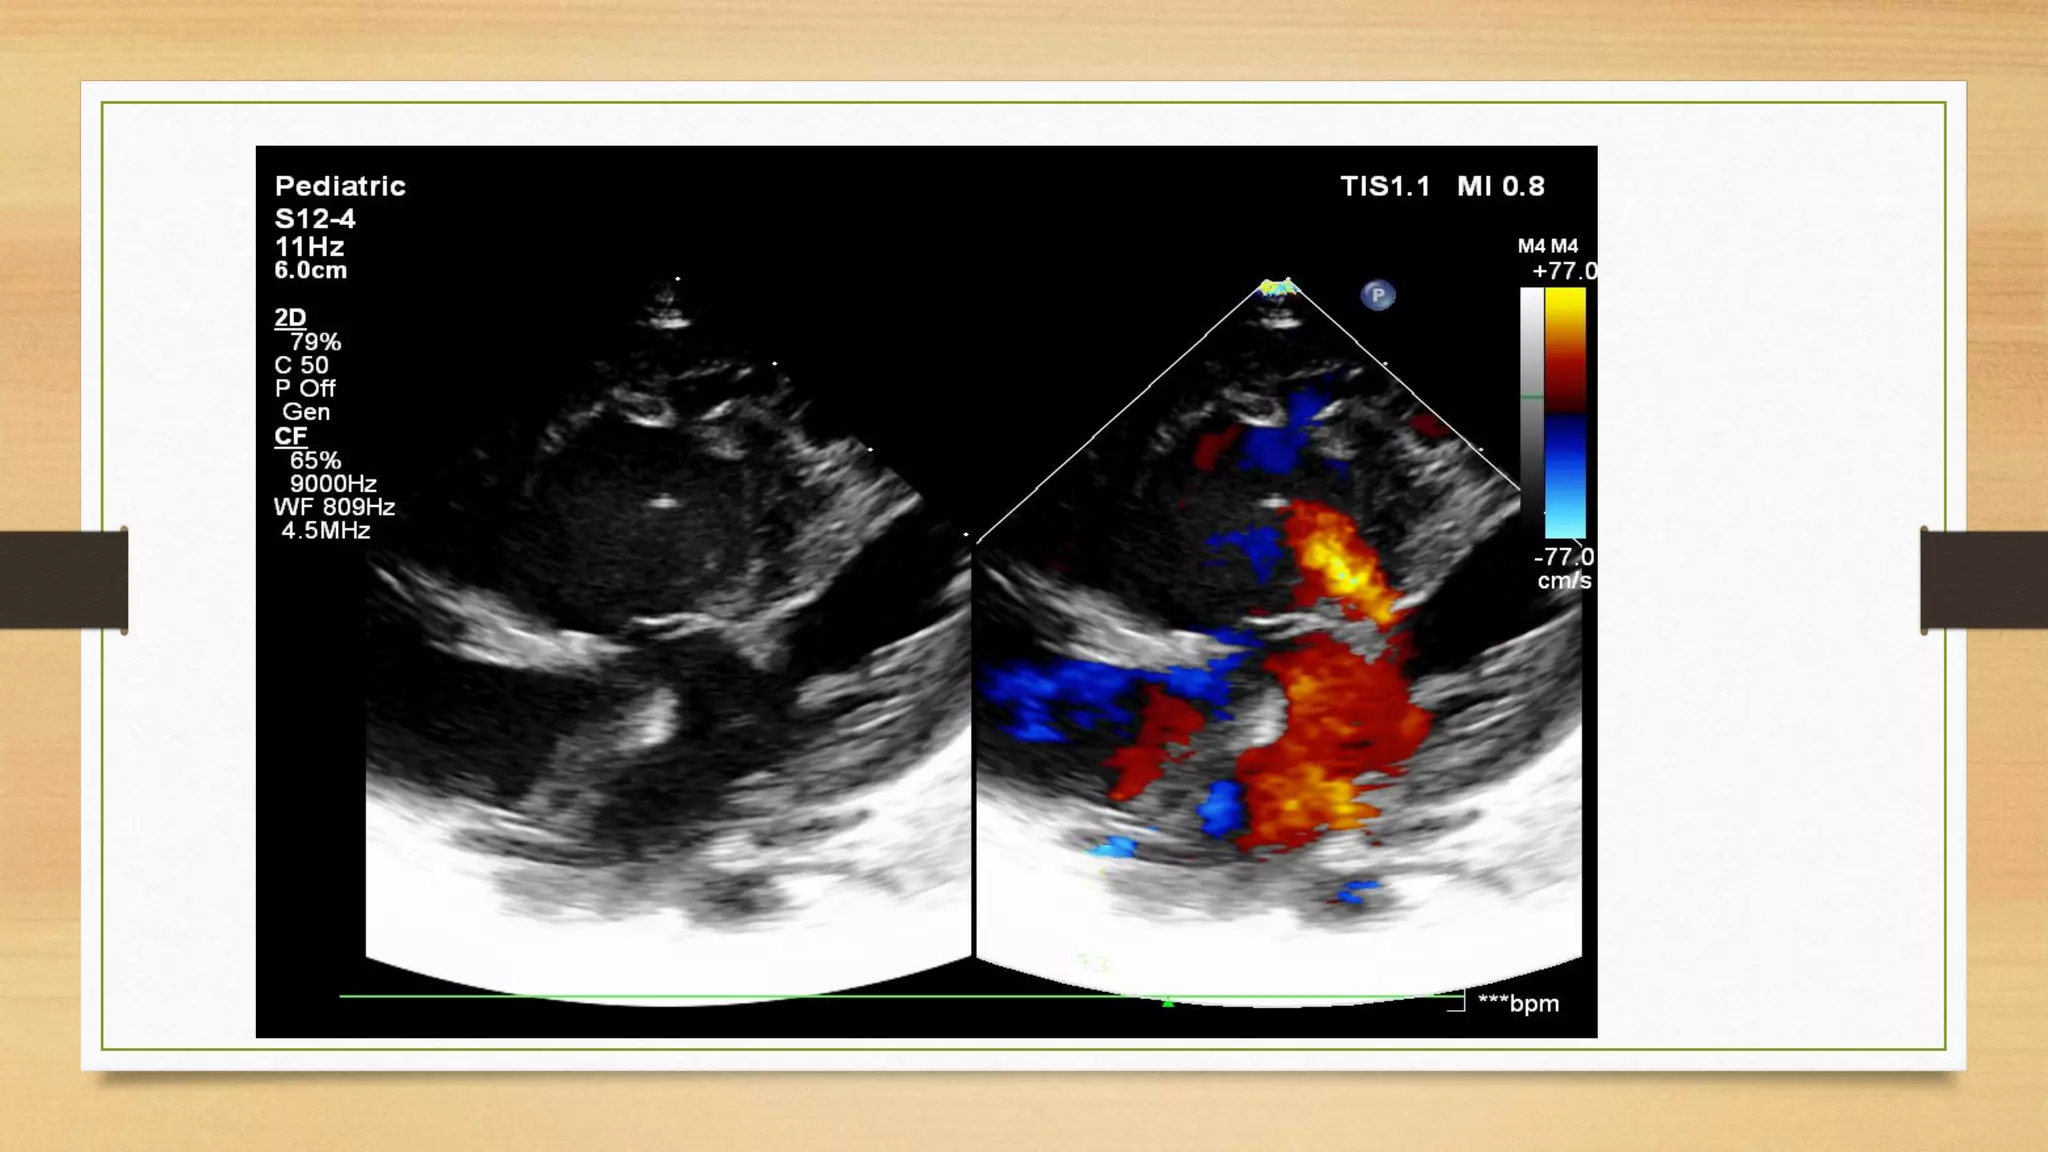

balanced AVSD Complete E D with TAPVC

Echocardiography

It is the key tool for the diagnosis and assessment of size of atrial and

ventricular septal defects, size of the ventricles (balanced or unbalanced),

estimation of the pulmonary artery pressures, presence and severity of AV valve

regurgitation and for associated lesions such as left superior vena cava, left or

right ventricular outflow tract obstruction, and heterotaxy syndrome.